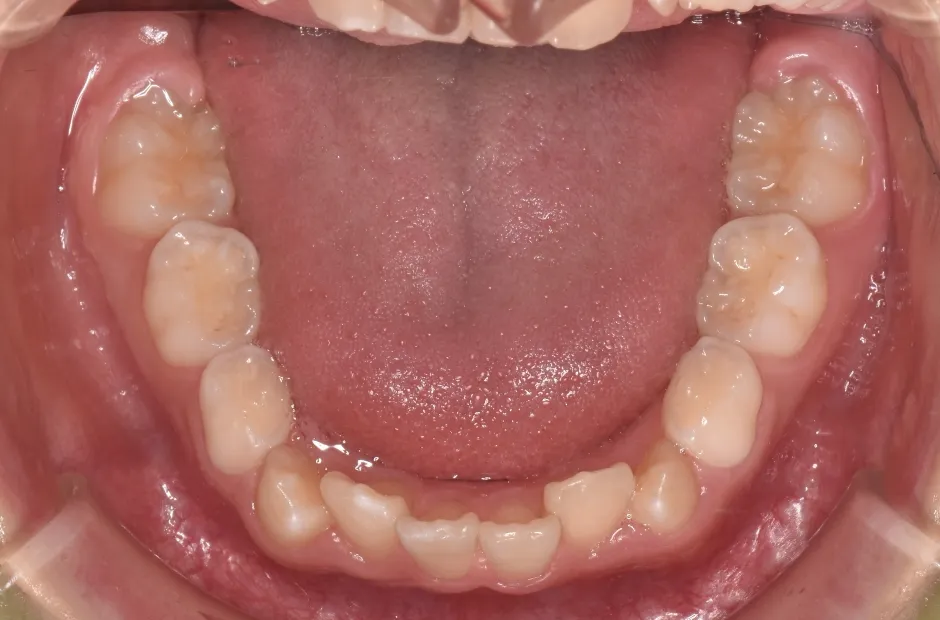

反対咬合

| 診断名・主訴 | 前歯反対咬合 |

|---|---|

| 年齢・性別 | 12歳・男性 |

| 治療期間・回数 | 1年半 18回 |

| 治療に用いた主な装置 | リンガルアーチ(前方誘導弾線) |

| 抜歯部位 | なし |

| 治療費 | 35万円(税抜) |

| リスク・副作用 | 装置による違和感・疼痛・歯肉退縮・歯根吸収・虫歯のリスクなど |